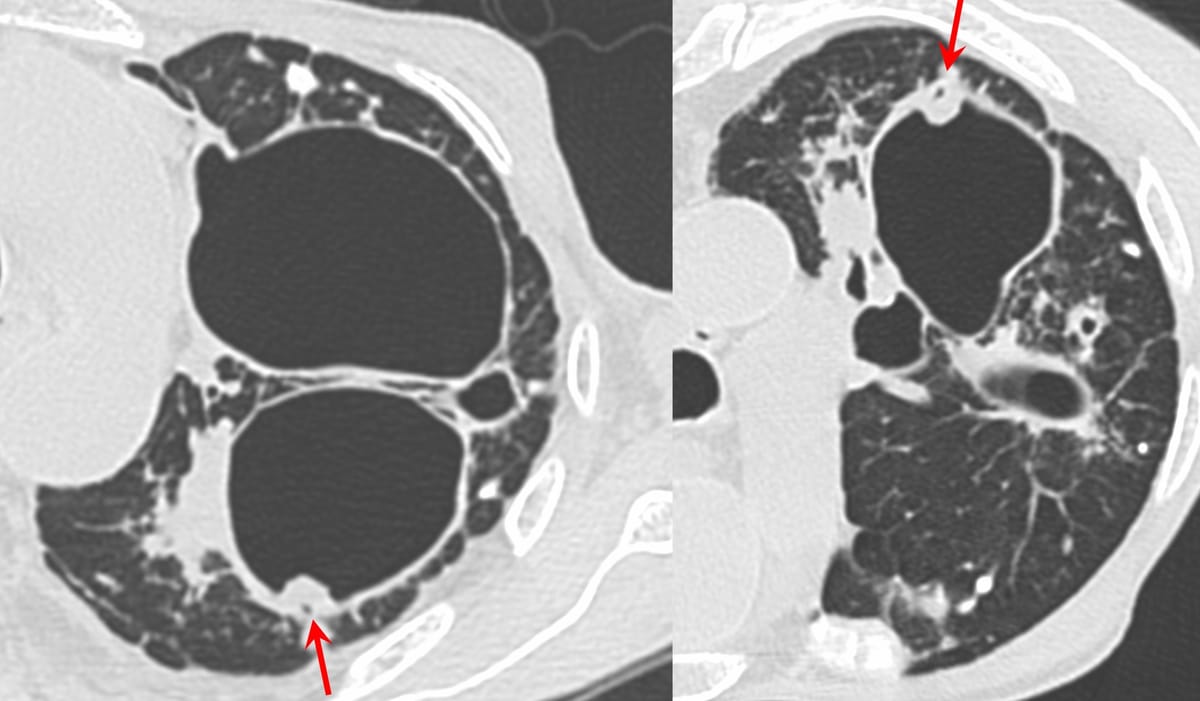

COD 137 - Validation of the "Scab-Like" Sign

The "scab-like" sign helps pick up early CPA/CCPA

429-years old with PTLD had fever and weight loss. CT in July 2025 showed a "scab-like" sign, suggesting chronic pulmonary aspergillosis (CPA). This was also discussed in Case of the Day 16 and in Case 20

Case 20: “Scab-Like” Sign for Chronic Cavitary Aspergillosis

Post-tuberculous cavities with the “scab-like” sign predicting chronic cavitary pulmonary aspergillosis